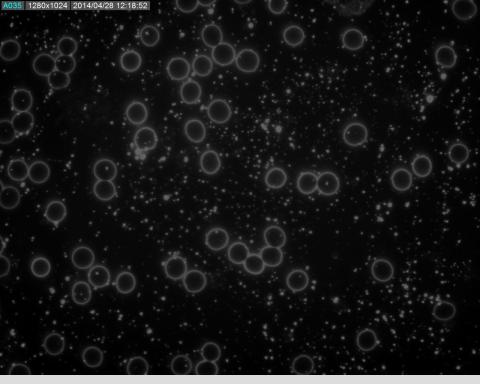

Čistá krv pod mikroskopom obsahuje plazmu, červené a biele krvinky, na 1000 červených má byť 1-4 bielych. Červené krvinky by mali byť pekné guľaté, rovnaké, oddelené. Takto vyzerá záťaž ťažkými kovmi pod darkfield mikroskopom, kovy sú biele svietivé útvary v plazme.

Červené krvinky majú tendencie utekať pred ťažkými kovmi, pretože ich to poškodzuje. V ich prítomnosti buď umierajú alebo ich membrána mení tvar na „ohryzené“. Biele krvinky, keďže reprezentujú imunitu, práve naopak ťažké kovy pohlcujú, v dôsledku toho hypersegmentujú a nakoniec umierajú.

tazkekovy